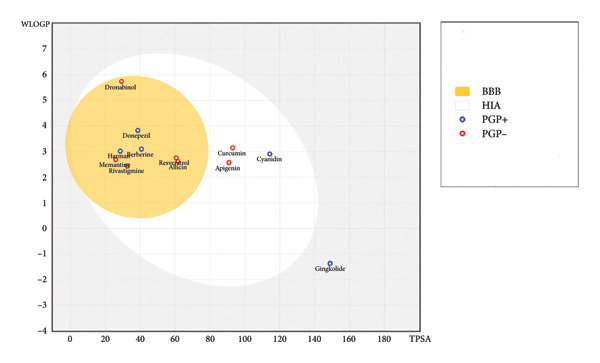

Most ligands, including 4‐tert‐amylphenol, allicin, apigenin, astragalosides, berberine, cannabidiol, curcumin, cyanidin, dronabinol, galantamine, harman, and resveratrol, demonstrated high GI absorption. Conversely, ginkgolide, ginsenosides, and hesperidin showed low GI absorption. BBB permeation varied, with 4‐tert‐amylphenol, allicin, astragalosides, berberine, cannabidiol, dronabinol, galantamine, harman, and resveratrol predicted as BBB permeant. Solubility (ESOL class) ranged from very soluble (allicin) to poorly soluble (dronabinol, ginsenosides), represented through Figure 1 which highlights the varying BBB and human intestine absorption (HIA) predictions.

Regarding drug‐likeness (Lipinski’s Rule of Five), many ligands (e.g., 4‐tert‐amylphenol, allicin, apigenin, berberine, curcumin, cyanidin, galantamine, ginkgolide, harman, and resveratrol) showed zero violations, indicating favorable oral bioavailability. However, astragalosides (2 violations), cannabidiol (1 violation), dronabinol (1 violation), ginsenosides (1 violation), and hesperidin (3 violations) exhibited deviations. Lead‐likeness also varied, with apigenin, cyanidin, and galantamine meeting criteria, while others showed violations. The bioavailability score was consistently 0.55 for most compounds, except hesperidin (0.17). Skin permeation rates also showed a wide range.